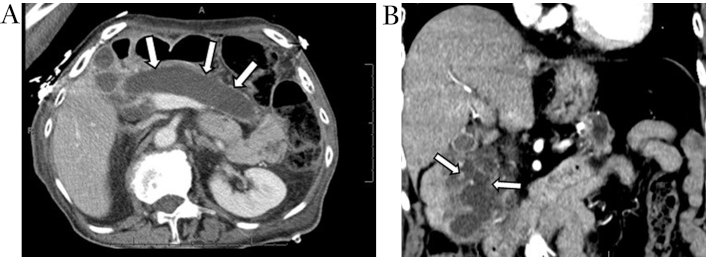

CT shows IPMNs as single or multiple cystic hypodense lesions. MD-IPMNs directly involve the MPD associated mucin hypersecretion resulting in ductal dilation over 5 mm often with progressive atrophy of overlying pancreatic parenchyma (Figure 4A and 4B). BD-IPMNs may be unilocular, multicystic, or may have a tubular morphology (Figure 5A). Mixed-type IPMNs have features of both the BD-IPMNs and MD-IPMNs (Figure 5B) [18]. On MRI, IPMNs are hyperintense on T2-weighted imaging and demonstrate low signal on T1-weighted imaging due to its mucinous content. Communication with pancreatic duct is commonly noticeable. Enhancing mural nodules and pancreatic ductal dilation are better identified on MRI when compared to CT imaging [54].

Main duct IPMN. Axial contrast-enhanced CT image (A) demonstrates diffuse marked dilation of the main pancreatic duct (white arrows). Coronal contrast-enhanced CT image (B) obtained 1-year later shows scattered enhancing mural nodules, a worry-some feature (white arrows). IPMN: intraductal papillary mucinous neoplasm

Metachronous pancreatic adenocarcinoma consistent with field-defect. Coronal MRCP image (A) demonstrates mixed IPMN with segmental dilation of main duct in the pancreatic head (arrowhead) and cystically dilated branch ducts in pancreatic head and tail. Axial contrast-enhanced CT image (B) obtained 3 years after Whipple procedure for adenocarcinoma of pancreatic head shows new focus of hypo-enhancing mass in the tail (white arrow) away from the previously documented main duct and branch duct IPMNs (arrowhead), consistent with the “field defect” phenomenon in the remnant pancreas. IPMN: intraductal papillary mucinous neoplasm

MD-IPMNs and mixed-typed IPMN demonstrate malignant transformation in approximately 45% of resected samples [6, 8]. In comparison with BD-IPMN, which exhibits a rate of advanced neoplasia in around 10–20% of resected specimens [6, 8]. Guidelines aimed at identifying worrisome and high-risk features for BD-IPMN have been set fourth, including the Sendai criteria followed by the Fukuoka guidelines which have been revised in 2017 and most recently the Kyoto guidelines [9, 55]. A recent study hypothesized that dilation of the uncinate duct is a radiographic indicator of high-risk disease, specifically IPMN associated with HGD or IC [56, 57]. IC may develop at a site distant from the primary location of the IPMN at a later stage, supporting the concept of field defect and dual carcinogenesis. This emphasizes the importance of radiological evaluation of the entire pancreas and further surveillance of the residual pancreas following resection of the cystic lesion [58].